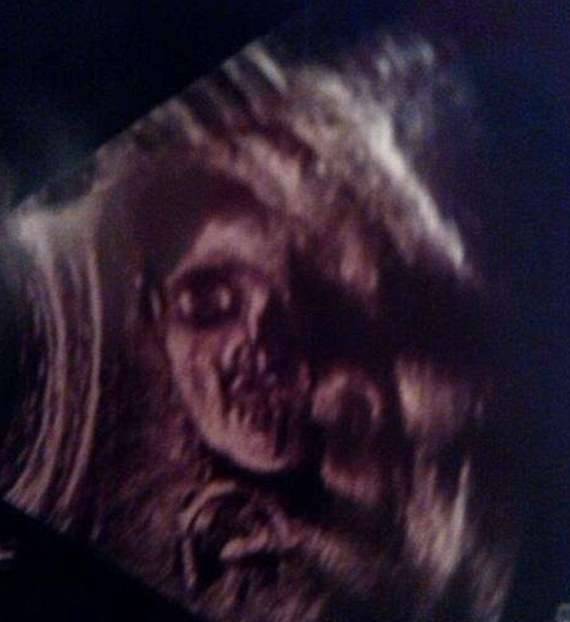

▼他有着巨大的嘴巴,用可怕的眼神盯着你,就像一个露着獠牙的怪物。